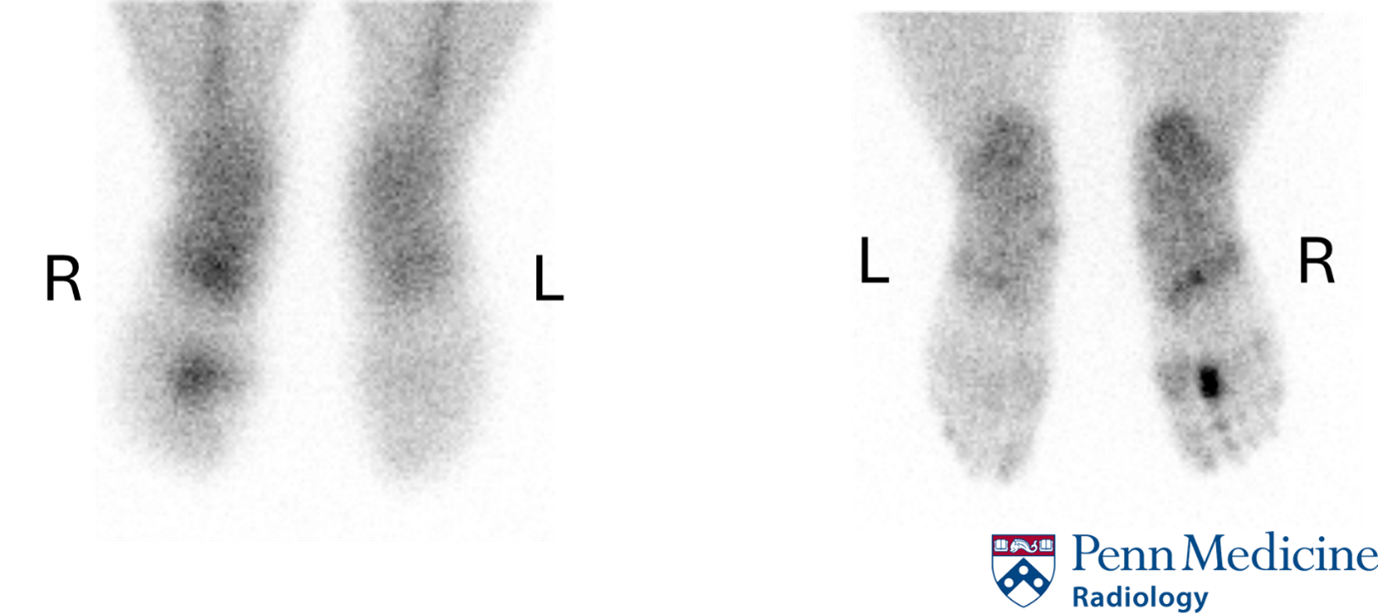

History: A 32-year-old woman presented to the outpatient physician for right foot pain. She had a history of remote hammertoe correction and was complaining of chronic pain in her right foot. She underwent a three-phase bone scan, which showed the following. Click images to enlarge.